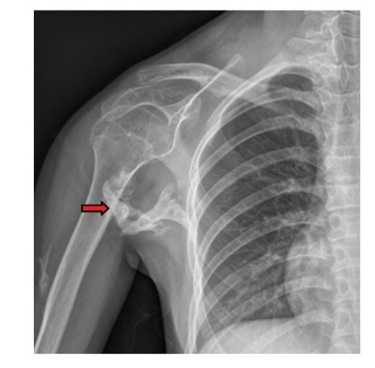

图2 患者右侧肩关节DR,红箭头示右上臂及右侧腋窝条块状高密度影,考虑骨化性肌炎改变(图源自文献)